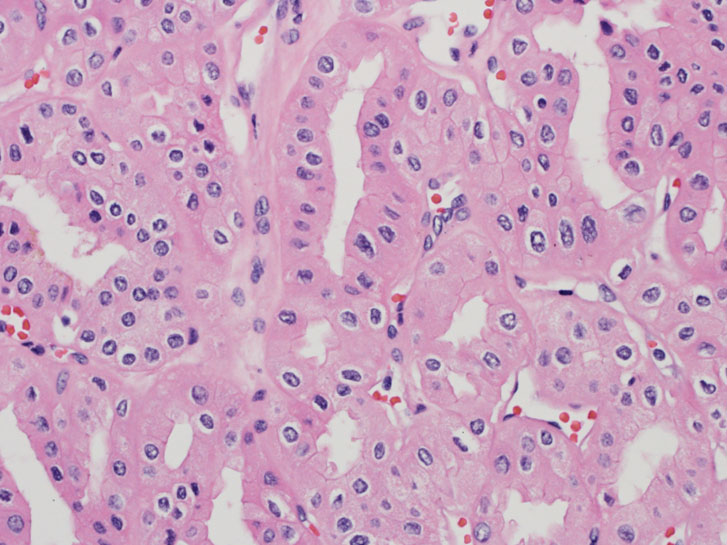

Consensus grade: I would not grade this tumor

| Pathologist 1 | I would not grade this tumor | Typical |

Chromophobic tumour |

| Pathologist 2 | I would not grade this tumor | Typical | |

| Pathologist 3 | I would not grade this tumor | Typical | |

| Pathologist 4 | I would not grade this tumor | Typical | |

| Pathologist 5 | I would not grade this tumor | Typical | |

| Pathologist 6 | I would not grade this tumor | Typical | |

| Pathologist 7 | I would not grade this tumor | Typical | |

| Pathologist 8 | I would not grade this tumor | Typical | |

| Pathologist 9 | I would not grade this tumor | Typical |

chromophobe |

| Pathologist 10 | I would not grade this tumor | Typical |

| Pathologist 11 | I would not grade this tumor | Typical | |

| Pathologist 12 | I would not grade this tumor | Typical | |

| Pathologist 13 | I would not grade this tumor | Typical | |

| Pathologist 14 | I would not grade this tumor | Typical | |

| Pathologist 15 | WHO/ISUP grade 2 | Typical | |

| Pathologist 16 | I would not grade this tumor | Typical | |

| Pathologist 17 | I would not grade this tumor | Typical | |

| Pathologist 18 | WHO/ISUP grade 4 | Typical |

chromophobe RCC-grading? |